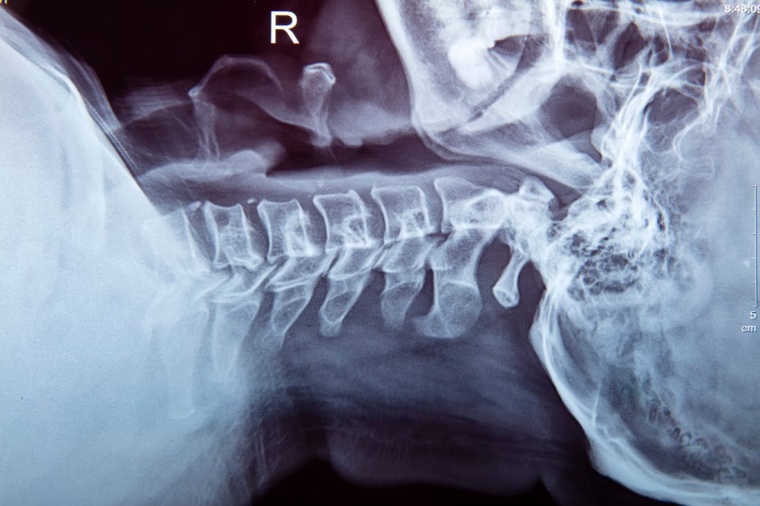

Die Prognose zur Genesung nach einer Rückenmarksverletzung (SCI) ist für die direkt Betroffenen und ihr Umfeld von großer Bedeutung. Bisher blieb sie aber ungenau. Forschern aus drei internationalen Rehabilitationszentren in Zürich, Murnau und Denver ist es nun gelungen, den Wert von Neuroimaging-Messungen für die Vorhersage der sensorischen und motorischen Genesung bei Menschen mit Tetraplegie aufzuzeigen. Die aus klinischen Magnetresonanztomographien (MRT) abgeleiteten Neuroimaging-Messungen erfassen das Ausmaß des unverletzten Nervengewebes neben der Rückenmarksläsion, die „spinalen Gewebebrücken“.